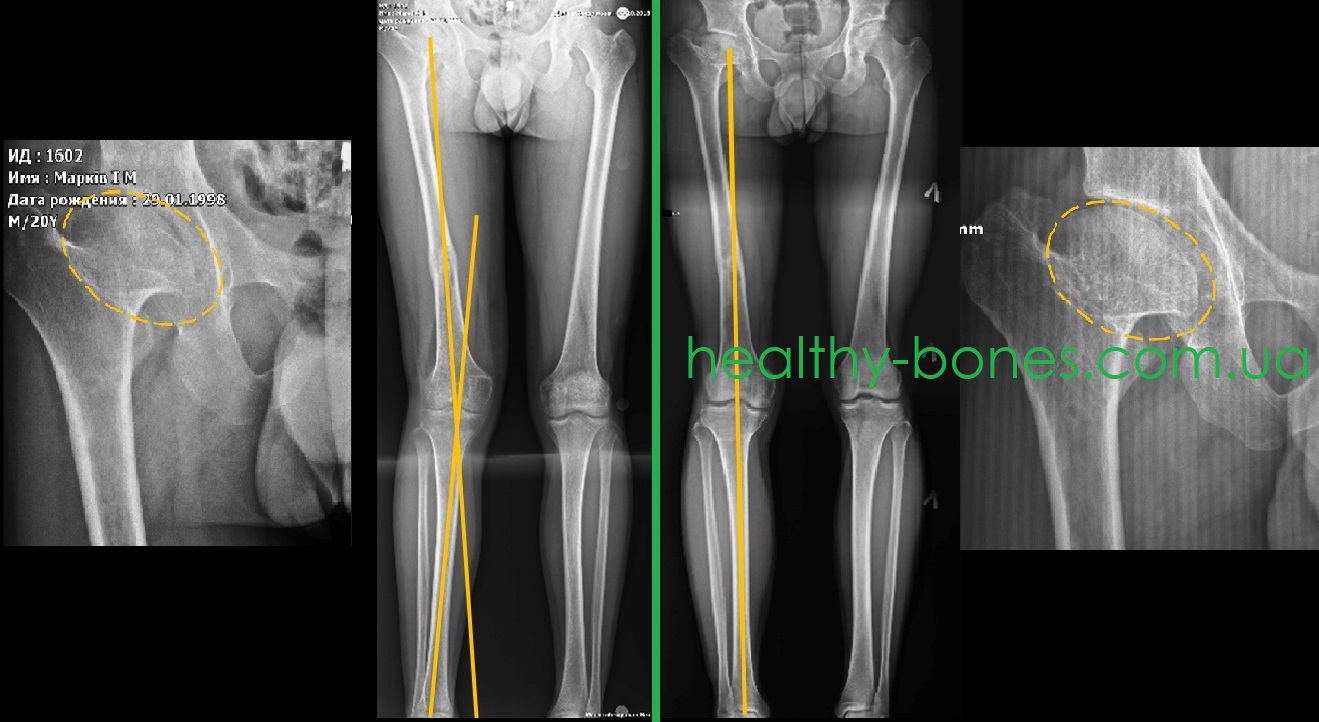

- значительное укорочение шейки правой бедренной кости с грибовидной деформацией головки, шеечно-диафизарный угол в пределах 130°

- укорочение правой нижней конечности до 5 см

- вальгусная деформация голени.

Нами было проведено этапное оперативное лечение – на первом этапе выполнено удлинение правой бедренной кости, а на втором – устранена вальгусная деформация голени.

Данные операции позволили максимально возможно восстановить осевую нагрузку правой нижней конечности, что позволило устранить болевой синдром в области правого тазобедренного сустава. После завершения лечения головка бедренной кости стала более округлой, что способствовало увеличению объема движений в суставе.